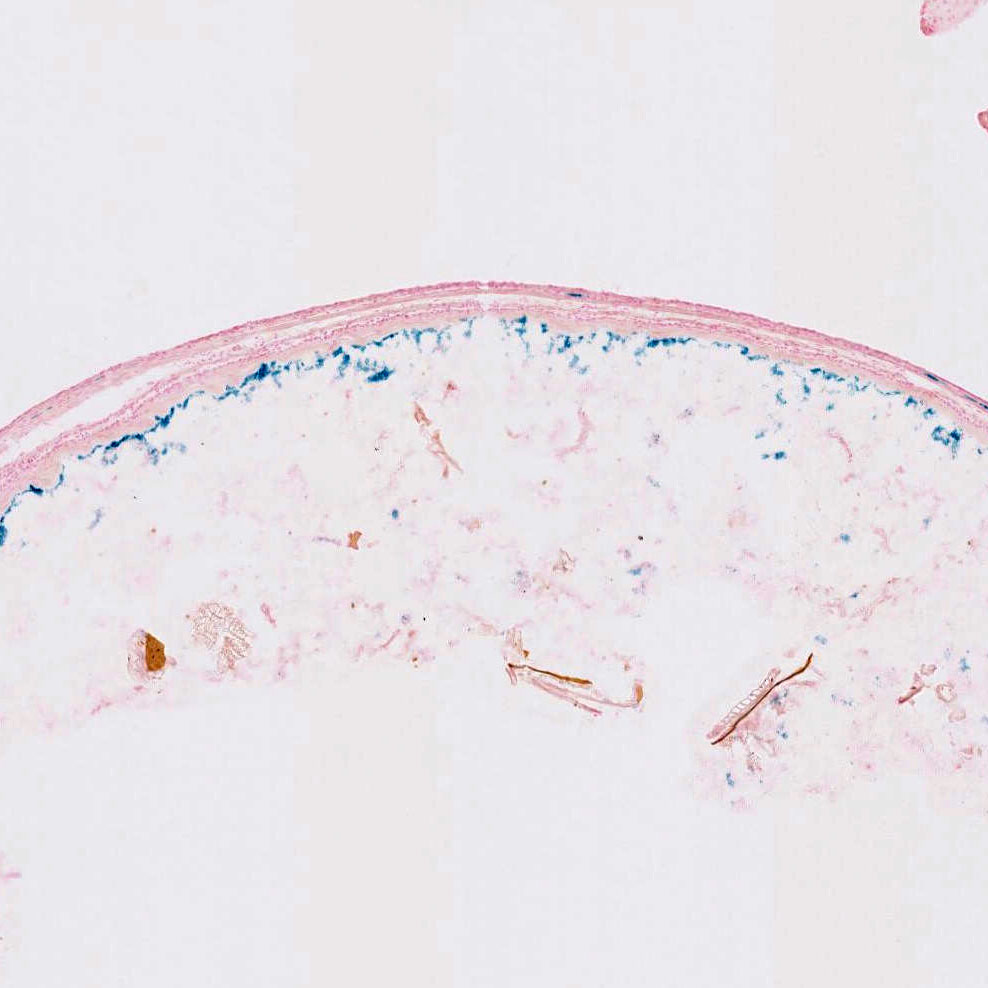

The bacterial Cre recombinase gene was inserted into the first exon of an expression cassette (clone 445) that contains all the introns, promoter regulatory elements, exons, and 2.5 kb of 5' and 2 kb of 3' flanking DNA of the astroglia-specific mouse glial fibrillary acidic protein gene. GFAP is not expressed from the transgene due to deletion of part of exon 1. Cre expression was detected in a small population of cells within the subependymal zone in the adult brain. No Cre expression or activity was detected during embryonic development or in the hippocampus.